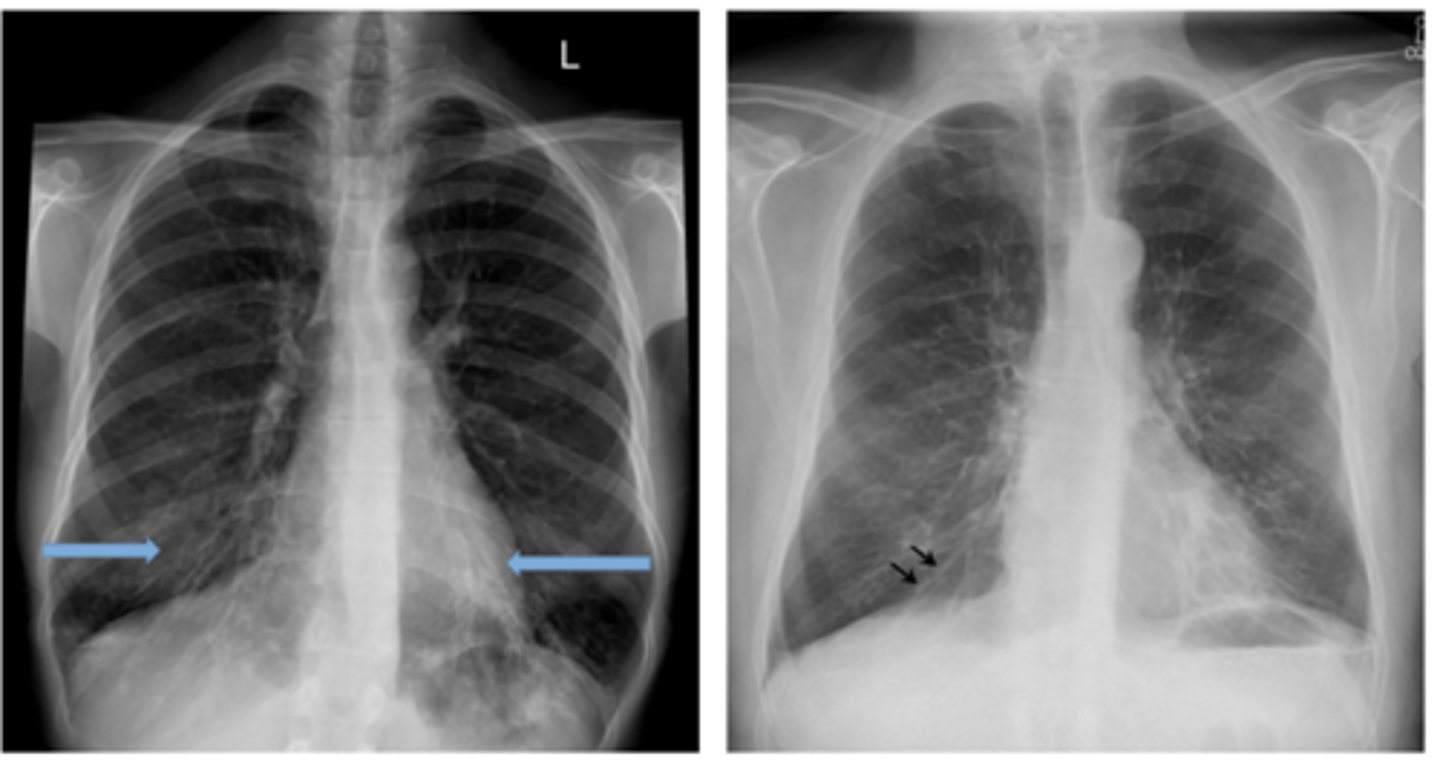

Pneumothorax (caused by stabbing)

visceral pleural line in the left chest (white arrows).

horizontal line along the base of the left hemithorax, which represents an air-fluid level (black arrows), showing that the patient has a hemopneumothorax.

2 key findings in this x-ray and dx

<p>2 key findings in this x-ray and dx</p>